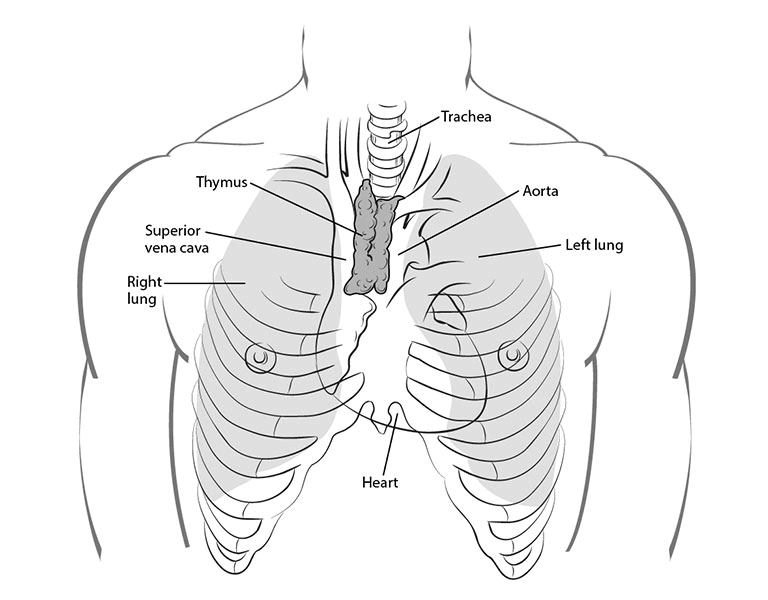

Thymic carcinoma is a rare and aggressive cancer that starts in the thymus gland, which is located in the upper part of the chest behind the breastbone. The thymus gland plays a role in the immune system by helping develop white blood cells called T-lymphocytes.

How is Thymic Carcinoma Diagnosed?

- CT scan or MRI for detailed imaging of the tumor and surrounding tissues